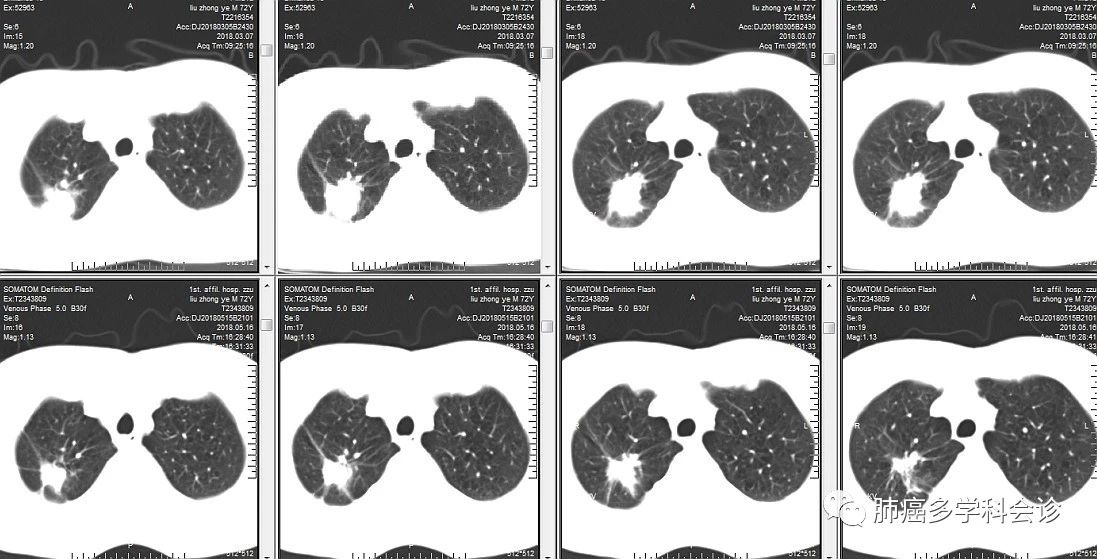

以下为患者在 PD-1抗体治疗前(上一行,2018-3-7)和治疗后(下一行,2018-5-16)胸部 CT 所显示的肿块大小,右上肺的肿块在肺窗(上图)和纵隔窗(下图)都明显退缩。